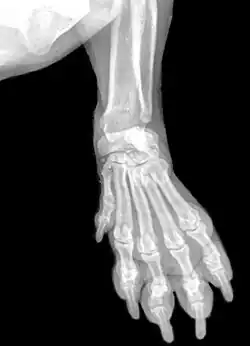

Кисть (анатомия)

Кисть в анатомии (лат. manus) — дистальная часть верхней конечности.

Скелет кисти составляют кости запястья, кости пясти и кости пальцев (фаланги). Запястье состоит из восьми коротких губчатых костей, расположенных в два ряда, по четыре в каждом ряду:

- верхний: ладьевидная (os scaphoideum), полулунная (os lunatum), трёхгранная (os triquetrum), гороховидная (os pisiforme);

- нижний: кость-трапеция (os trapezium), трапециевидная (os trapezoideum), головчатая (os capitatum), крючковидная (os hamatum) кости[1].

Следующий ряд костей кисти образуют пястные кости. Костей пять, по числу пальцев. Основания их соединяются запястными костями. Фаланги пальцев так же, как и пястные кости, являются короткими трубчатыми костями. В каждом пальце имеется по три фаланги: основная (проксимальная), средняя и концевая или ногтевая (дистальная). Исключение составляет большой палец, который образован только двумя фалангами — основной и ногтевой. Между пястной костью и фалангами каждого пальца образуются подвижные сочленения.

Кисть имеет три отдела: запястье (carpus), пястье (ossae metacarpi) и пальцы (digitus mani)[2].